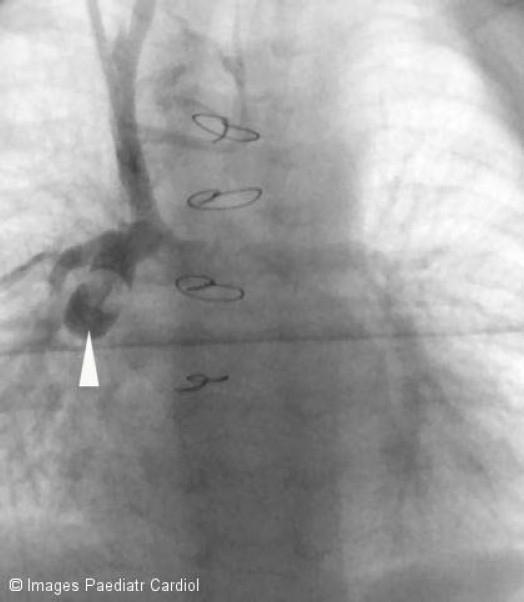

全腔静脉肺动脉连接术前先天性心脏病的心脏导管评估

Cardiac catheter assessment of congenital heart disease prior to total cavopulmonary connection.

This paper summarises the rationale behind cardiac catheter assessment prior to surgical completion of the Fontan circulation in hearts with univentricular pathology.

摘要